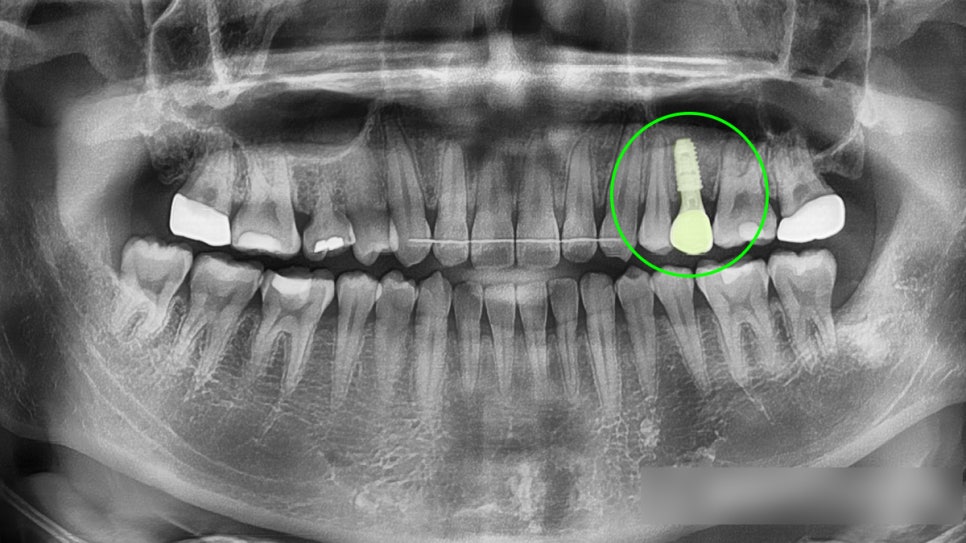

중간에 엑스레이 촬영으로

치아들의 반응을 살펴주며

안전하게 배열했습니다.

크게 문제가 되는

부분은 없습니다.

치아가 원활하게 이동되어

확보된 자리로 임플란트

수술을 진행했습니다.

그리고 식립을 해둔 상태에서

잇몸 위로 나사 뚜껑(힐링어버트먼트)을 올려

잇몸이 올바르게 형성될 수 있는

환경을 만들었습니다.

이렇게 임플란트가 잘 식립되었어도,

잇몸뼈와 유착되는 기간이 어느정도 필요합니다.